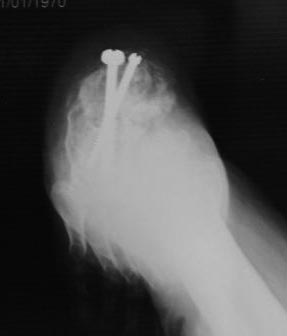

[Ortho] Постравматическая деформация пяточной кости

Уважаемые коллеги.Операция была произведена 22.01.16г. только

сегодня имеется возможность отправить. L-образный доступ. . при ревизии

подтаранный сустав сохранен, поэтому линейная остеотомия, подкожная

ахиллотомия. . подготовка ложа, и смещенный отломок спущен вниз к ложу,

но  до конца не смогли. фиксирован двумя винтами. по медиальной

поверхности рубец плотно спаянный с костной осколькой пока не трогали

из-за опасения инфицирования, после заживления раны потом будем думать

что делать.